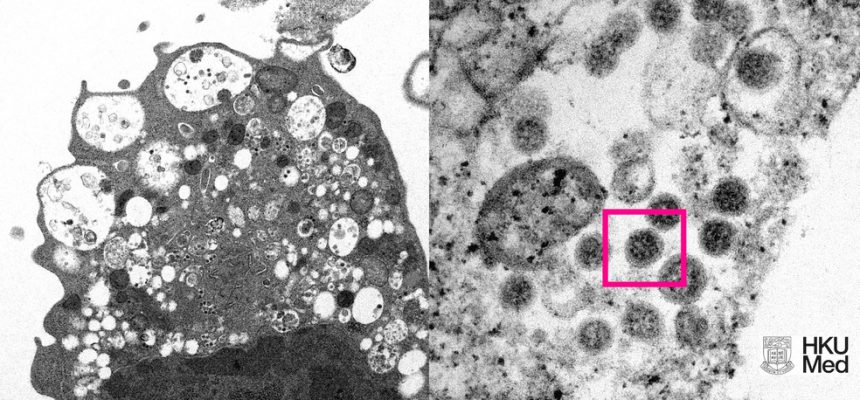

O primeiro caso de paciente com a subvariante BA.2 da ômicron na cidade de São Paulo foi confirmado nesta segunda-feira (7) pela Secretaria municipal da Saúde. O exame foi realizado no dia 28 de janeiro em um morador de Santo André, no Grande ABC, que utilizou uma Unidade Básica de Saúde na Zona Leste da capital. Com este, são três casos da subvariante no estado e seis no país.

O paciente é um homem de 22 anos que tomou duas doses da vacina contra a Covid em 15 de agosto e 26 de novembro e que ainda não está apto a receber a dose de reforço, já que é necessário aguardar 6 meses para tomar a terceira dose.

Segundo a secretaria, ele disse ter sentido sintomas leves e que cumpriu o isolamento social recomendado assim que os sintomas tiveram início. Segundo o paciente, ele não viajou e nenhum familiar adoeceu.

Oficialmente, a Secretaria da Saúde Paulista tem dois casos registrados, um em Guarulhos e outro em Sorocaba. O terceiro será este da capital, que entra no balanço do estado hoje.